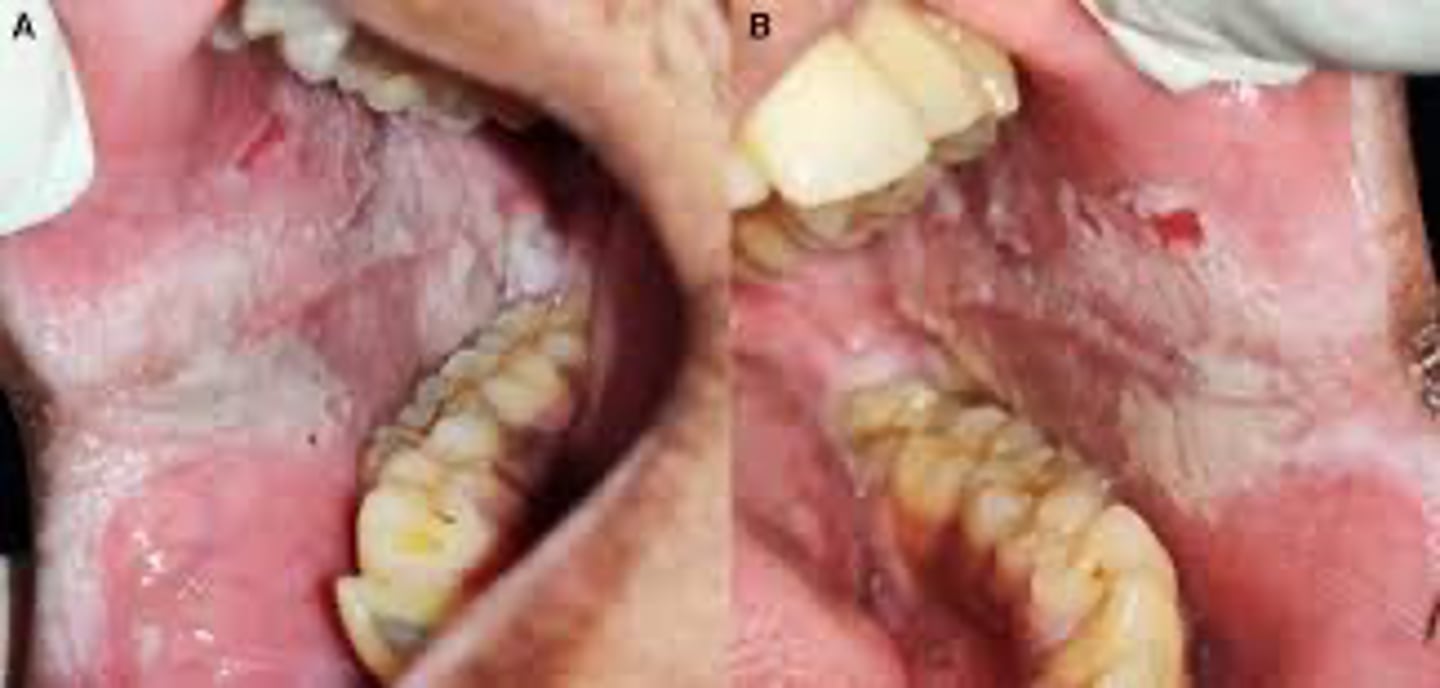

A patient presents with bilateral white lacy striations on the buccal mucosa.

What ist he most likely diagnosis?

lichen planus